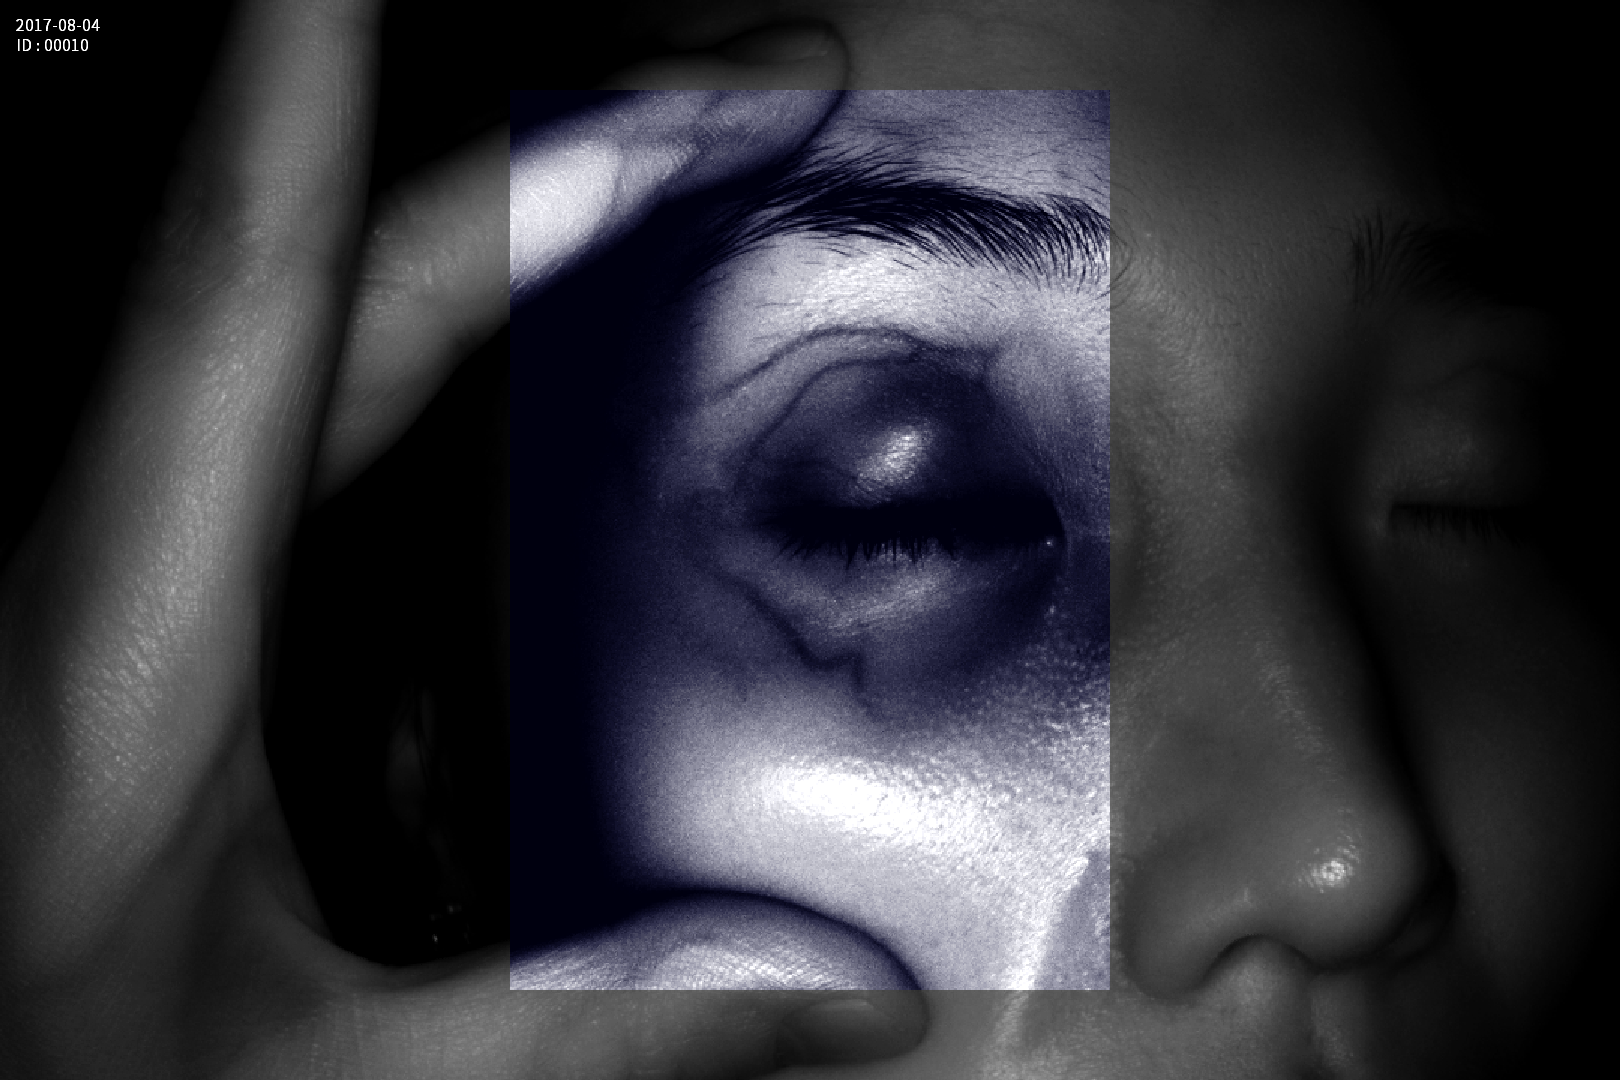

Grad mare de detecție a venelor greu vizibile până la 10 mm adâncime (inclusiv vene faciale)

Calitate înaltă a imaginii având o rezoluție de 1280 x 800 pixeli

Imaginea venelor este proiectată pe monitorul propriu în timp real si ajută la identificarea corectă și precisă

Multiple aplicații de vizualizare vene atât la sugari cât și la pacienții obezi sau în urgențe indiferent de tonul de culoare a pielii

- Camera de vizualizare cu tehnologie infrarosu